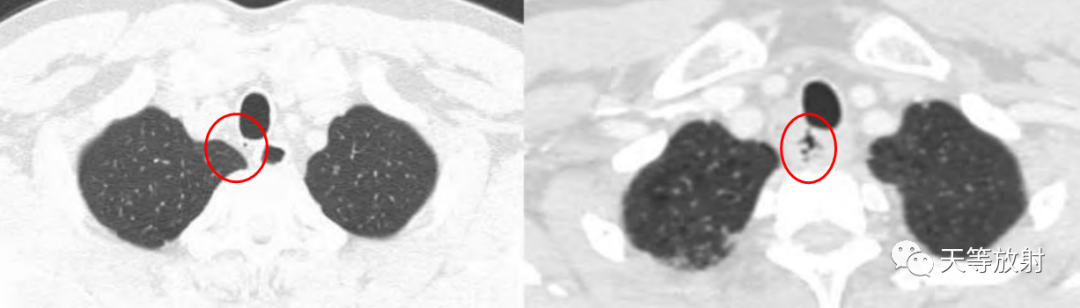

上图:胸廓入口处气管旁纵隔内局限含气影,复查片显示含气影内见细小分隔,囊影内壁较光整。

上图:CT值囊影与气管内气体CT值相同,为气体密度影。